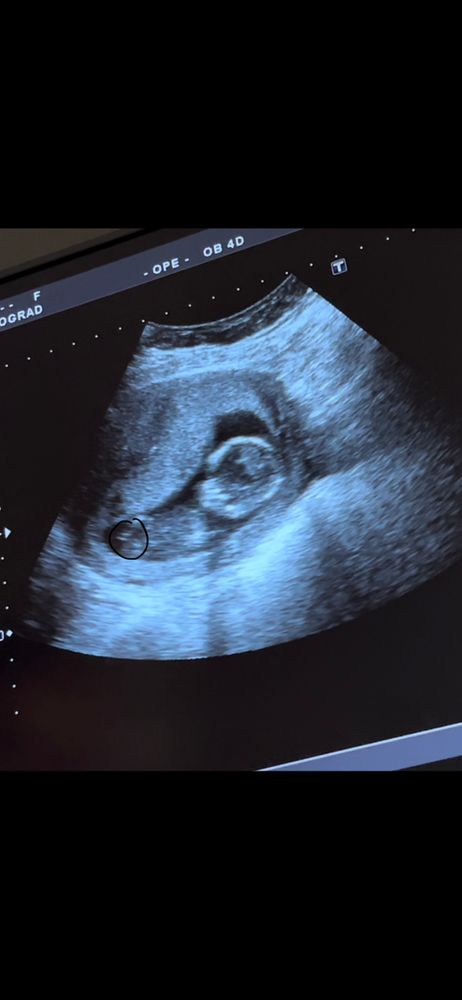

прикрепляю фото.. простите за качество, это скрин с видео)

второе фото это сегодня) я обвела половой бугорок) вроде девчачий 😂